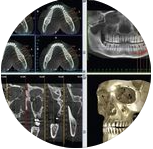

Este curso está diseñado para cirujanos dentistas que buscan perfeccionar sus habilidades quirúrgicas en el manejo de procedimientos avanzados de cirugía bucal, con especial énfasis en la cirugía dentoalveolar y exodoncias complejas. El programa se compone de 4 módulos teóricos y 4 módulos prácticos, integrando conocimiento actualizado con entrenamiento clínico en condiciones reales. En el área teórica, el curso aborda: -Anatomía aplicada a la cirugía bucal -Osteotomía y odontosección -Diseño de colgajos y manejo de tejidos blandos -Complicaciones y farmacología en cirugía bucal La formación práctica se desarrolla en pabellón clínico, permitiendo al participante aplicar técnicas quirúrgicas bajo supervisión, fortaleciendo la toma de decisiones y el manejo integral del paciente. Además, el curso incluye un Hands On en sala, realizado en entorno controlado, utilizando modelos en cadáver y tejido porcino, donde se entrenan habilidades clave como: -Diseño de colgajos -Técnicas de sutura -Manejo de tejidos blandos en cirugía bucal Requisitos de ingreso: Ser cirujano dentista con título chileno o validado por una institución chilena. Este curso representa una oportunidad única para avanzar desde la teoría a la práctica clínica real, elevando el nivel quirúrgico y la confianza profesional en procedimientos complejos.